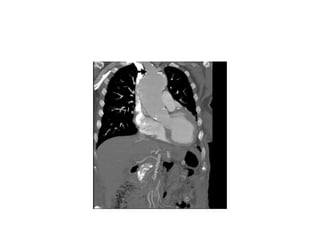

•   Symptom Comment

•   Experience of pain Almost ubiquitous—96% of patients report pain

•   Location of pain Anterior characterizes ascending dissection;

•   posterior characterizes descending dissection

•   Severity of pain “10 out of 10”

•   Onset of pain Abrupt (distinguishes from MI)

•   Quality of pain “Tearing” quality

•   Variability of pain Classical patterns common, but not invariable;

•   4% of patients experience no pain

•   Waxing and waning Variability in severity of pain reflects physiological

•   of pain (decrease in aortic wall tension with rx of BP) and

•   anatomic events (spontaneous re-entry).

•   Pleuritic component Reflects pericardial and pleural inflammation

•   Cardiac ischemia True anginal/infarction symptoms may occur from

•   involvement of RCA

•   Abdominal pain Vigilant search for intestinal ischemia essential

•   (lethal phenomenon)

•   Renal ischemia Usually asymptomatic, except in case of infarction

•   Leg pain From involvement of iliac artery by dissection

•   process

•   Paralysis of legs From spinal cord ischemia or peripheral nerve ischemia

•   (paraplegia)

•   Syncope From either:

•   Involvement of head vessels

•   Tamponade

•   Acute aortic insufficiency

•   Vaso-vagal response to pain

•   Dyspnea Acute aortic insufficiency poorly tolerated